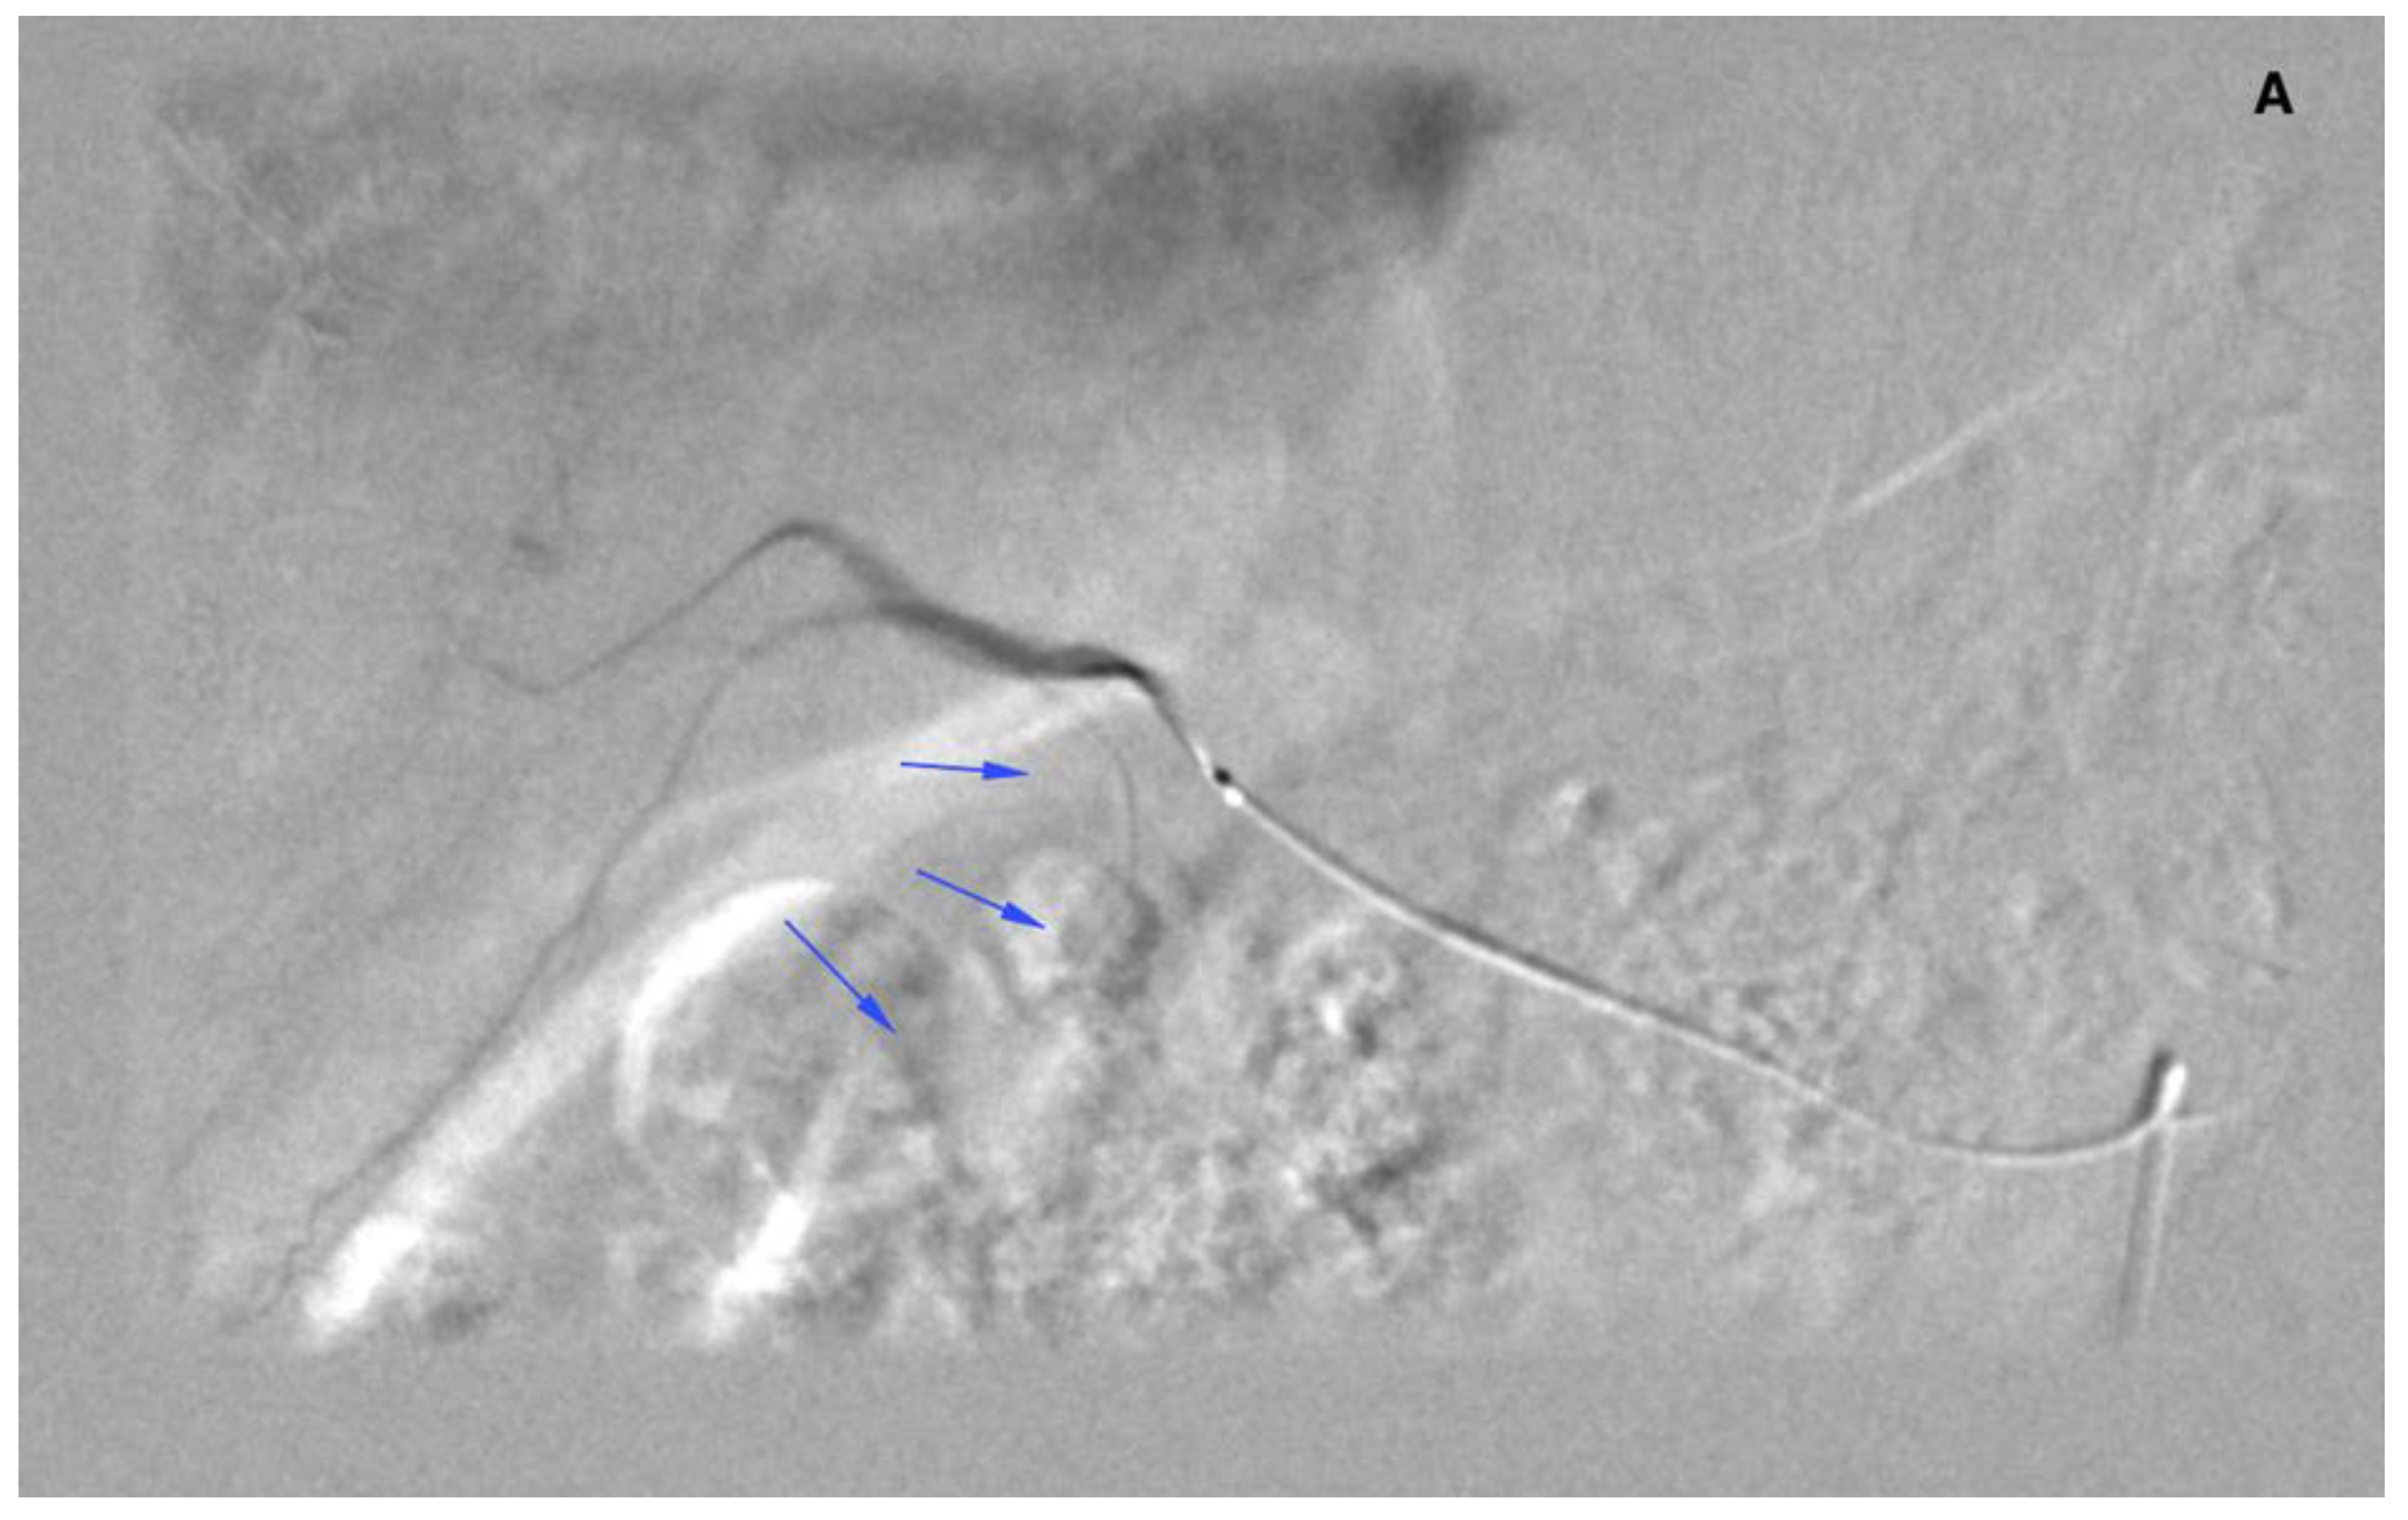

Figure 3.

Angiogram of the right hepatic artery. (A) Initially, single CA is visible (arrows) originating from the right hepatic artery division. (B) After embolization, another artery reveals multiple intrahepatic anastomoses to the gallbladder wall, and needs to be embolized. (C) There is insufficient embolization of both CA, and (D) retraction of the microcatheter reveals another CA originating proximally to the right hepatic artery division (arrows).